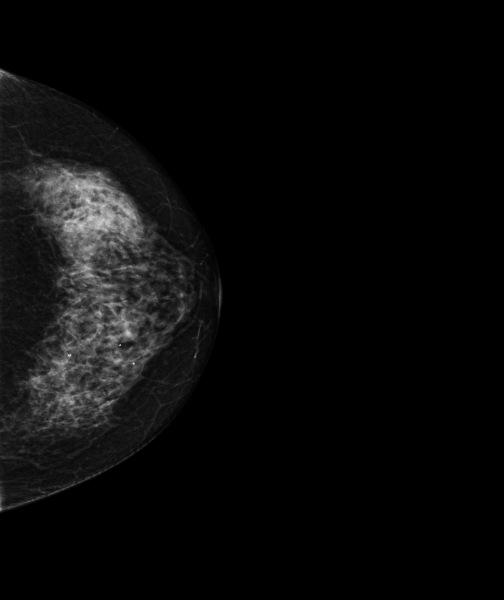

Femme de 69 ans, examen pour dépistage du cancer du sein.

MammoScreen indique une lésion externe du sein droit à type de distorsion architecturale.

L’échographie retrouve une formation hypoéchogène à contours irréguliers de 10mm avec rigidité à l’étude élastographique.

La biopsie mammaire effectuée indique un carcinome canalaire infiltrant SBR 1, RH+, HER2-, avec activité proliférative à 5%.Grâce au score de 5, MammoScreen alerte le radiologue et permet la détection du carcinome.